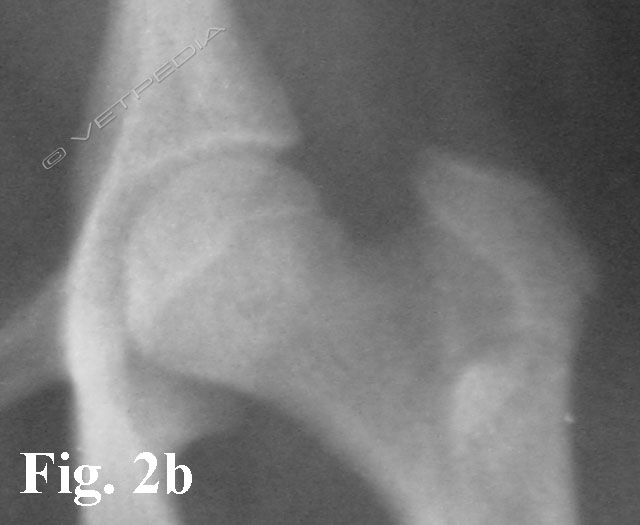

{{/_source.additionalInfo}}La necrosi asettica della testa del femore è anche denominata malattia di Legg Calvè Perthes e necrosi avascolare della testa del femore. Si tratta di un'affezione ortopedica coinvolgente l’articolazione coxofemorale di cani di razza toy o di piccola taglia durante il periodo dell’accrescimento, ad interessamento più frequentemente monola